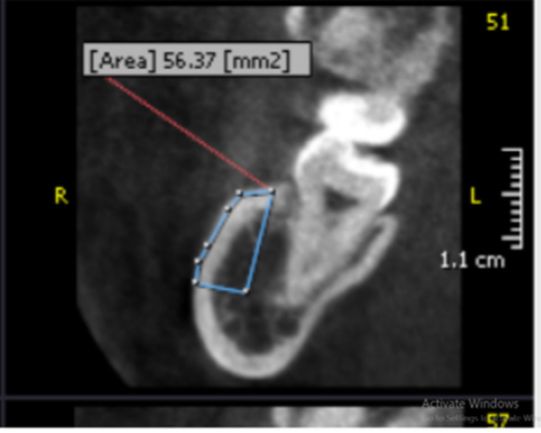

Determination of the Volume and Density of Mandibular Ramus as a Donor Site Using CBCT